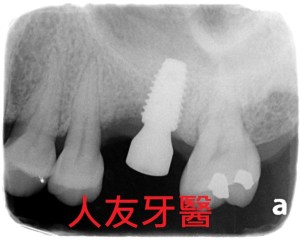

植牙真的可以現拔現種嗎 ?!